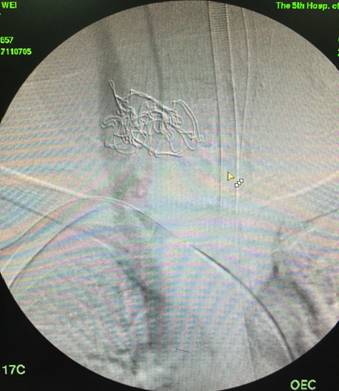

在此危急关头,王兵教授当机立断,转为腔内治疗,经右侧股动脉入路,行右颈部动脉造影,明确出血位置后可通过植入覆膜支架封堵动脉破口,起到止血目的,待出血控制后再次清理创面,进而完成整个手术。造影过程中,王颖医师及吴斐医师冒着暴露在射线下的风险轮流按压伤口止血。功夫不负有心人,通过超选择造影终于找到元凶:右侧锁骨下动脉近甲状颈干分支出破裂出血, 可见明显造影剂外渗,更为意外的是同时锁骨下静脉也有损伤,导致右侧锁骨下动静脉瘘!(图3)

▲图3